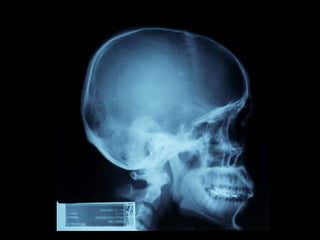

Este documento describe brevemente la historia de la radiografía y los rayos X, y explica que existen diferentes tipos de radiografías y aplicaciones en odontología, incluyendo radiografías intraorales y extraorales. También proporciona ejemplos de actividades para identificar estructuras que aparecen en radiografías dentales de acuerdo a su radioopacidad.